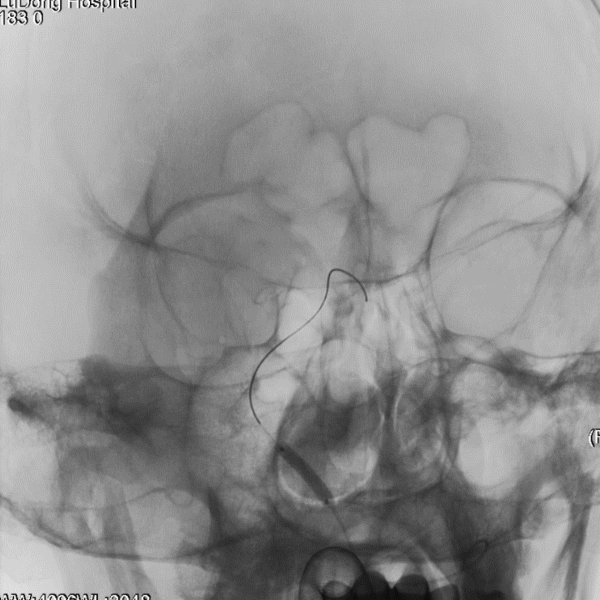

入院影像检查

导丝怎么扩【载药时代 球扩天下】NOVA DES®颅内药物洗脱支架在症状性颅内动脉狭窄中的应用—烟台鲁东医院使用体会二例!_https://www.jmylbn.com_新闻资讯_第4张

RVI

RICA

导丝怎么扩【载药时代 球扩天下】NOVA DES®颅内药物洗脱支架在症状性颅内动脉狭窄中的应用—烟台鲁东医院使用体会二例!_https://www.jmylbn.com_新闻资讯_第5张

LICA

LVI

重要影像结论:双侧颈内动脉起始段轻度狭榨,左侧椎动脉V4段重度狭窄;左侧大脑后动脉颅内段闭塞。

导丝怎么扩【载药时代 球扩天下】NOVA DES®颅内药物洗脱支架在症状性颅内动脉狭窄中的应用—烟台鲁东医院使用体会二例!_https://www.jmylbn.com_新闻资讯_第6张

LVA狭窄90%

重要影像结论:左椎动脉V4重度狭窄,大于90%,右椎动脉纤细远端闭塞。